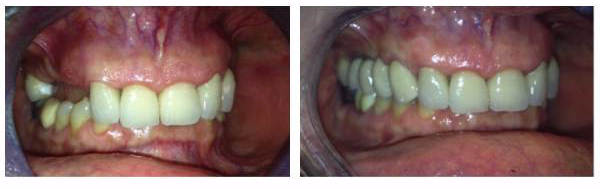

Lo schema con impianti inclinati nell'arcata mandibolare (inferiore) per evitare i forami mentali e ottenere in ogni caso un considerevole stabilità primaria per il carico immediato.

Le soluzioni più moderne rispetto al Toronto Bridge originale prevedono un trattamento abbastanza simile tra le due arcate. Gli impianti, se necessario, si inseriscono non paralleli tra loro ma con una inclinazione di circa 30° allo scopo di evitare i forami mentali nell'arcata inferiore e i seni mascellari nell'arcata superiore: l'obiettivo è ottenere una buona stabilità primaria degli impianti (necessaria anche per il carico immediato) anche in assenza di struttura idonea nelle zone posteriori evitando trattamenti più complessi con innesti di osso. Il posizionamento disparallelo/inclinato prevede necessariamente una componentistica del sistema implantare che permetta successivamente la protesizzazione degli impianti disparalleli. Infatti per gli impianti inclinati è prevista un protesizzazione con doppio moncone, un primo inclinato rispetto all'asse lungo dell'impianto (generalmente di 17°, 30° o addirittura 40-45°) ed un secondo in asse con l'emergenza del primo.